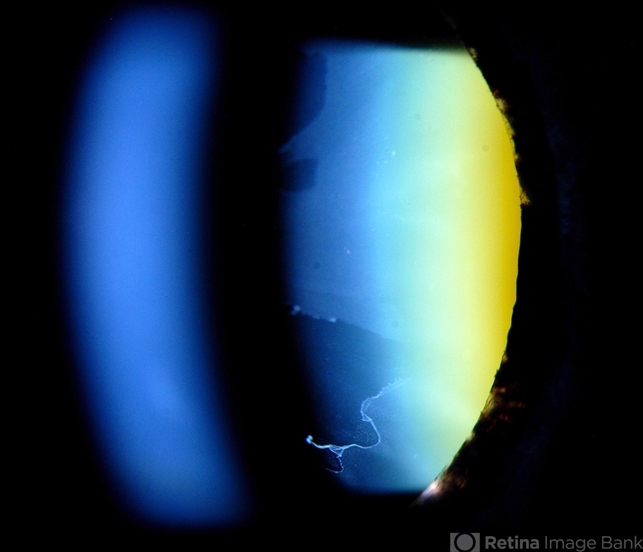

- Photo slit lamp biomicroscope

- Patient's VA 20/50 with pinhole no improvement. Patient will have cataract surgery in the future. Notice pseudoexfoliation ring centrally.